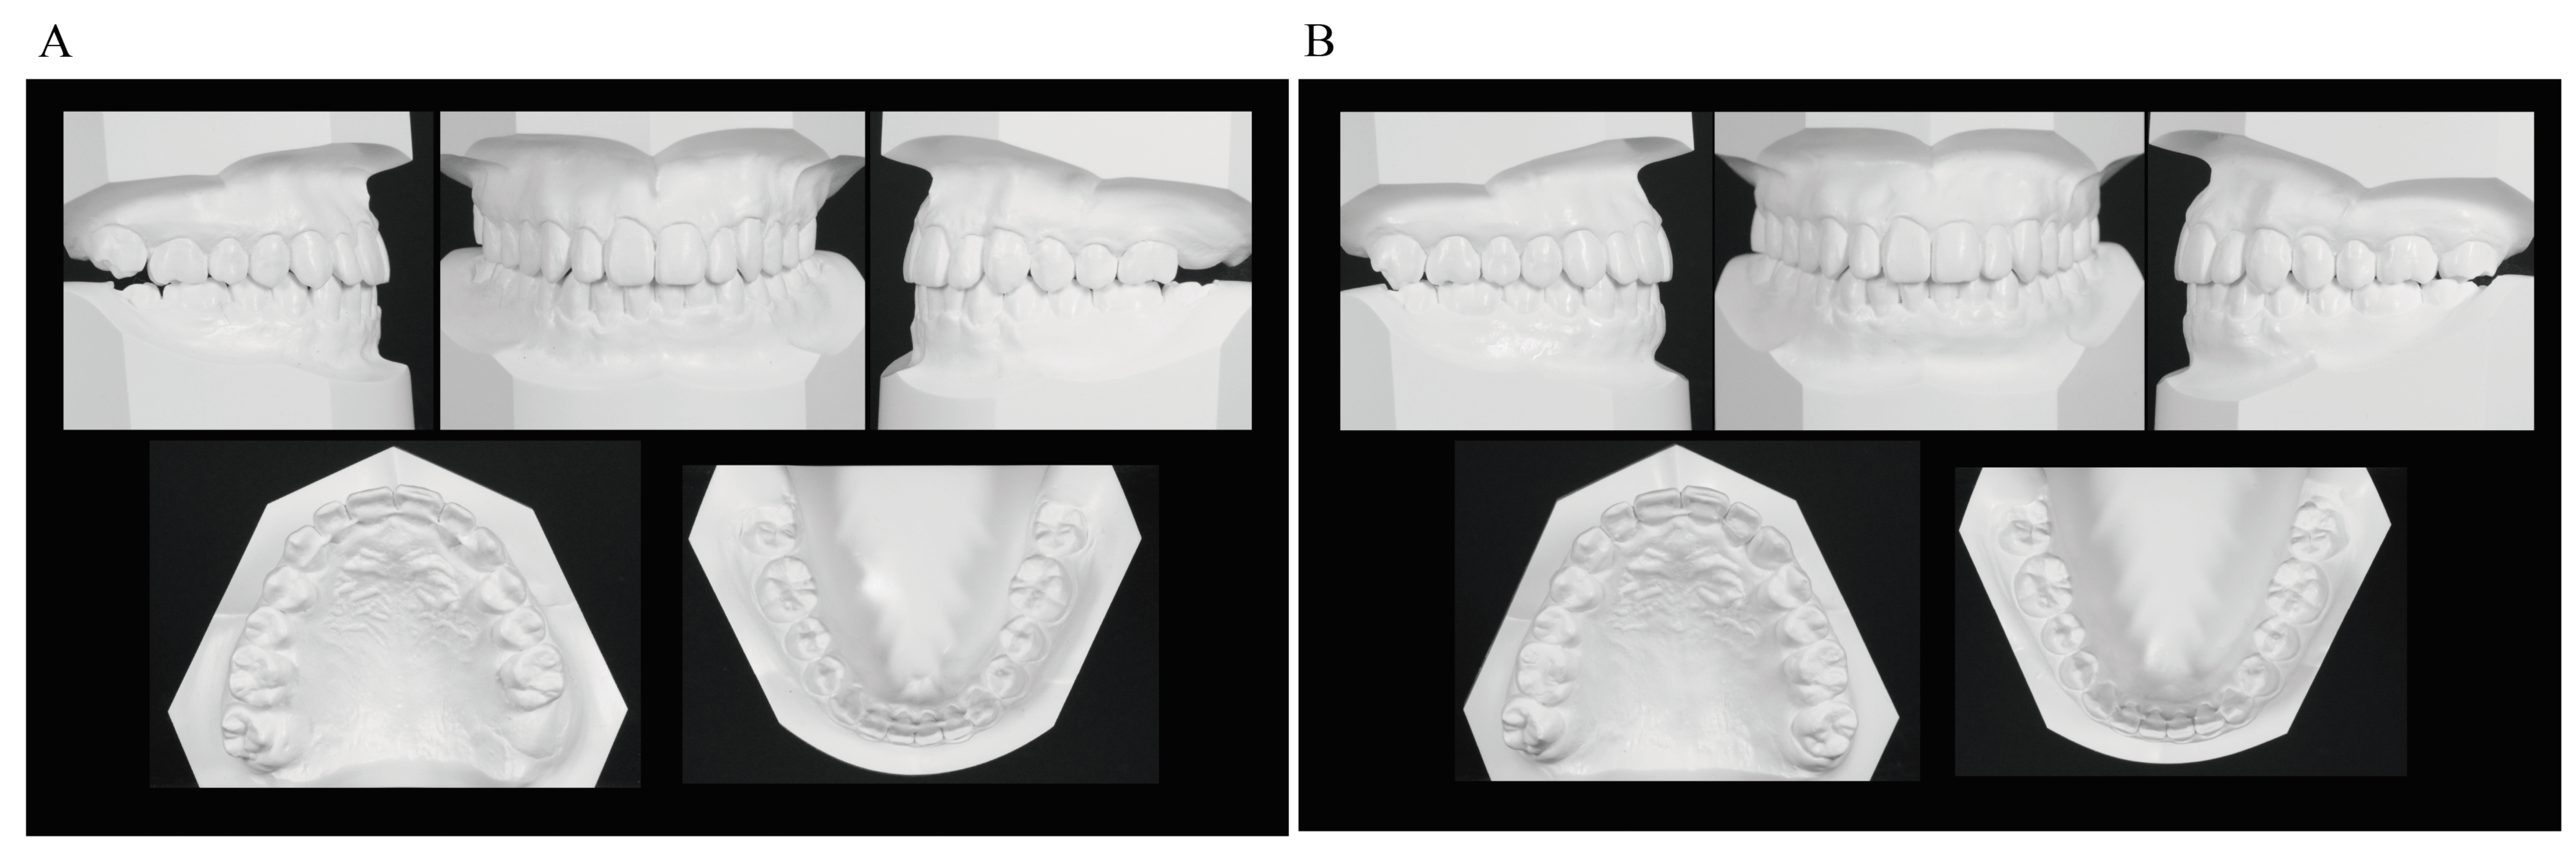

Figure 4. Measurement points and lines used for determining the mesiodistal position and axial inclination angles of the maxillary first molars. A′, intersection of the palatal plane and the perpendicular line from point A; ptm′, intersection of the palatal plane and the perpendicular line from ptm; Mo, midpoint of the occlusal surface of the maxillary first molars; Ms, intersection of the palatal plane and the perpendicular line from the midpoint of the occlusal surface of the maxillary first molars; Mp, line connecting the midpoint of the occlusal surface of the maxillary first molars and the midpoint of the mesial and distal root apexes; NF, palatal plane.

The mesiodistal positions and axial inclination angles of the maxillary first molars were also measured (Figure 4). Mesiodistal measurements were as follows: A′-ptm′ 51.0 mm, A′-Ms 32.5 mm for the right and 28.0 mm for the left, and ptm′-Ms 18.5 mm for the right and 23.0 mm for the left (the left one was approximately 4.5 mm more mesial than the right one). As described by Byloff et al. [16] and Mayara et al. [17], the line connecting the midpoint of the occlusal surface of the maxillary first molars and the midpoint of the mesial and distal root apexes was defined as the maxillary first molar axis (Mp), and the angle between the palatal plane and the maxillary first molar axis was defined as the maxillary first molar axial inclination angle (α). The inclination angle was 83.0° on the right and 88.0° on the left, indicating that the more mesially located left maxillary first molar was more mesially inclined (Table 1).

Lateral cephalometric radiography showed the following changes in the anteroposterior position of the maxillary first molars before and after the use of the Hyrax-type expander: A′-Ms from 32.5 mm to 33.0 mm for the right and from 28.0 mm to 33.0 mm for the left, and ptm′-Ms from 18.5 mm to 19.0 mm for the right and from 23.0 mm to 19.0 mm for the right. Thus, the right first molar showed no change in position while the left first molar was moved distally by about 4.5 mm to almost the same position as the right one. The axial inclination angle of the right maxillary first molar was unchanged from 83.0° while that of the left first molar decreased from 88.0° to 83.0°, indicating that the mesially inclined left first molar was caused to slightly incline distally (Figure 10 and Table 1).